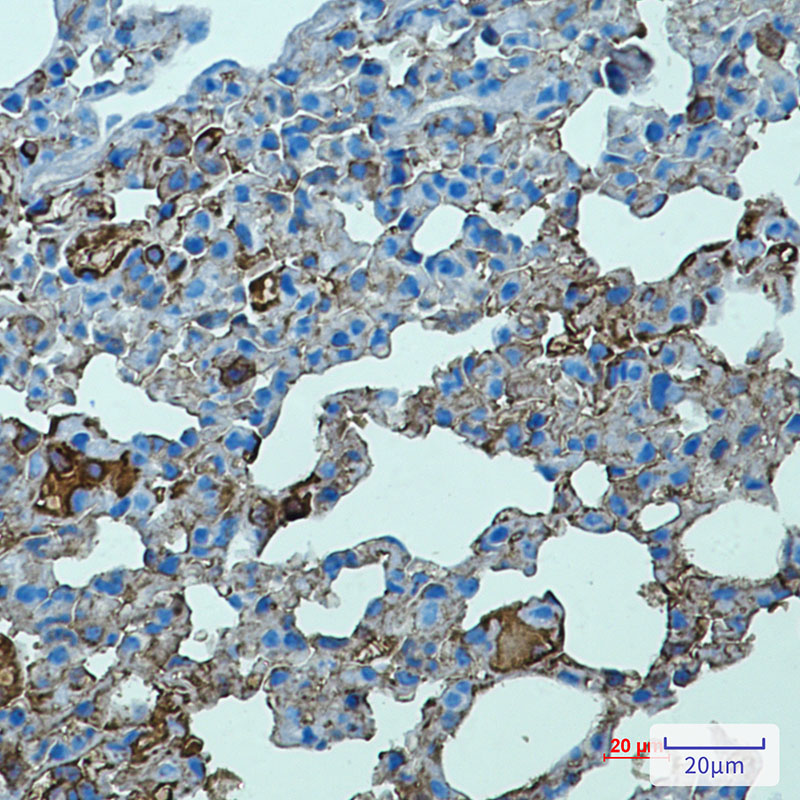

- Immunohistochemistry analysis of paraffin-embedded mouse lung using Toll Like Receptor 2 antibody.High-pressure and temperature Sodium Citrate pH 6.0 was used for antigen retrieval.